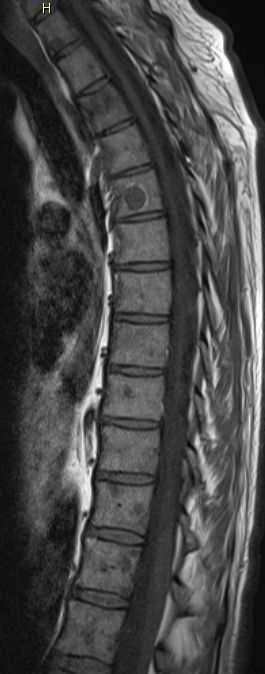

| Knochen - Metastasierung | ![]() |

![]() |